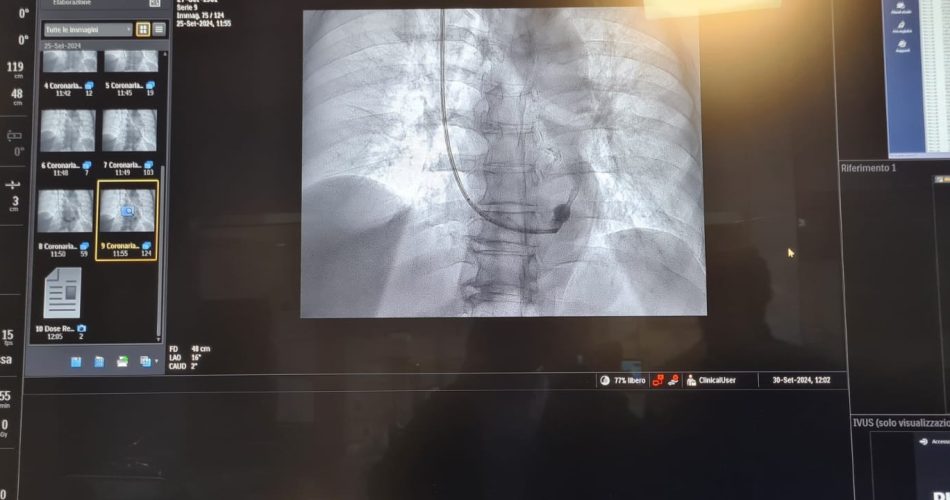

stent

“Abbiamo eseguito questo intervento invasivo ma non chirurgico – ha spiegato Bonfantino – in un paziente di 63 anni, in anestesia locale, che è consistito nell’impianto di uno stent metallico (reducer), a forma di clessidra, attraverso la vena giugulare, all’interno del seno coronarico, cioè la vena che sbocca nell’atrio destro del cuore e che drena tutto il sangue venoso di origine cardiaca, per poi raggiungere i polmoni ed essere ossigenato. Questa procedura – ha aggiunto -trova indicazione in quei pazienti coronaropatici sintomatici, che lamentano angina pectoris nonostante terapie farmacologiche ad alto dosaggio. La presenza di tale sintomatologia, anche assumendo una terapia farmacologica ottimizzata, determina un aumentato rischio ischemico cardiaco e genera grande frustrazione per i pazienti che non sono quindi in grado di svolgere in serenità le normali attività quotidiane”, ha concluso.

L’impianto dello stent reducer in sala è stato coordinato dal dottor Maurizio Turturo, responsabile della UOS Emodinamica, e dal dottor Francesco Cassano. “Grazie alla particolare morfologia dello stent, a forma di clessidra – ha detto Turturo – si determina un rallentamento del drenaggio venoso cardiaco, permettendo la persistenza nel cuore di sangue ancora ossigenato e quindi il rilascio di una maggiore quantità di ossigeno al muscolo cardiaco. Ciò determina, in un’alta percentuale di casi, la risoluzione dei sintomi anginosi del paziente e il sensibile miglioramento della qualità di vita del paziente”. L’esecuzione di tale procedura interventistica è un ulteriore obiettivo centrato dal Dipartimento di Cardiologia della ASL, diretto dal dottor Franco Massari, che assicura ai pazienti cardiopatici un’assistenza sempre di alta qualità e al passo con le nuove tecnologie.